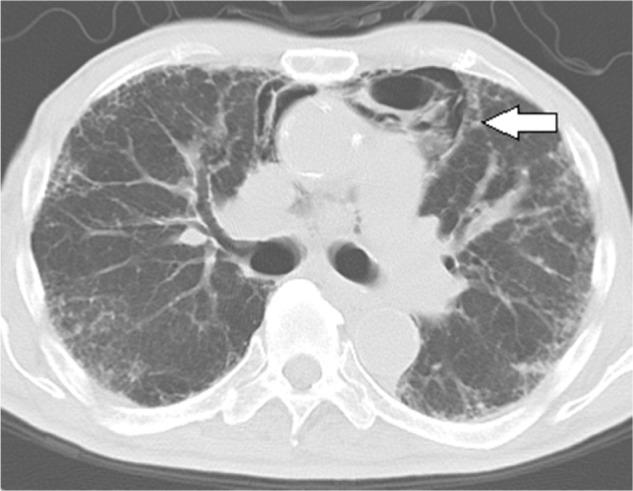

We report a case involving an 83-year-old man with interstitial lung disease who developed atypical pneumomediastinum caused by gas replacement of diminished fat. The patient presented with a complaint of worsening symptoms of respiratory difficulty since a diagnosis of chronic eosinophilic pneumonia 5 months back. He had been under observation with no particular treatment for 5 months. Computed tomography performed on admission revealed pneumomediastinum. When the current scan was compared with that obtained 5 months ago, it was evident that the fat surrounding the mediastinum had been replaced by gas density. There was no mediastinal enlargement, pneumothorax, or pneumopericardium. Because the patient was elderly, home oxygen therapy was initiated for the interstitial pneumonia with no steroid therapy. Computed tomography performed 10 months after discharge showed the reappearance of mediastinal fat and no evidence of gas density. This case is unique because the pneumomediastinum was distinct from spontaneous pneumomediastinum caused by alveolar air leaks and resembled the vacuum phenomenon caused by intervertebral disc degeneration.